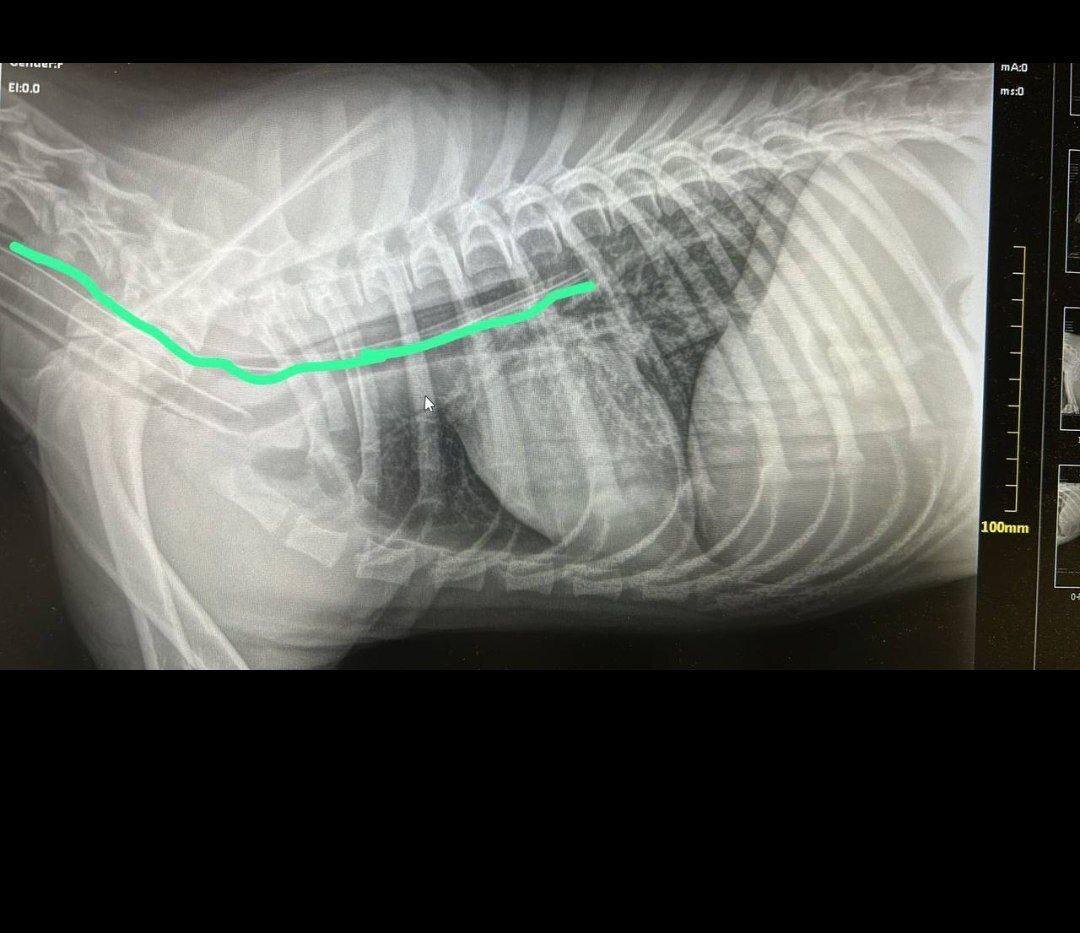

Пса с переломом черепа, гниющими ранами с опарышами, следами веревки и залитыми кровью глазами нашли 2 августа. Его подобрали и с трудом нашли ветклинику, которая взялась за такой тяжелый случай. Бониса буквально вытащили с того света. Сейчас более 2000 волонтеров ищут живодера.